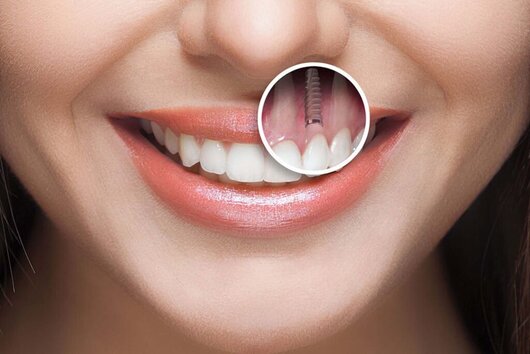

Aceasta procedura moderna pres ... | | | | | |  Implant dentar Implant dentar |  | Dent Park - Clinica stomatologica Bucuresti

Ce este implantul dentar - sol ... | | | | | |  Odontoterapie Odontoterapie |  | Dent Park - Clinica stomatologica Bucuresti

Consultatii Prima vizita: exa ... | | | | | |  Implanturi dentare Implanturi dentare |  | Opera Dental - Clinica stomatologica, Bucuresti

Parodontologie Endodo ... | | | | | |